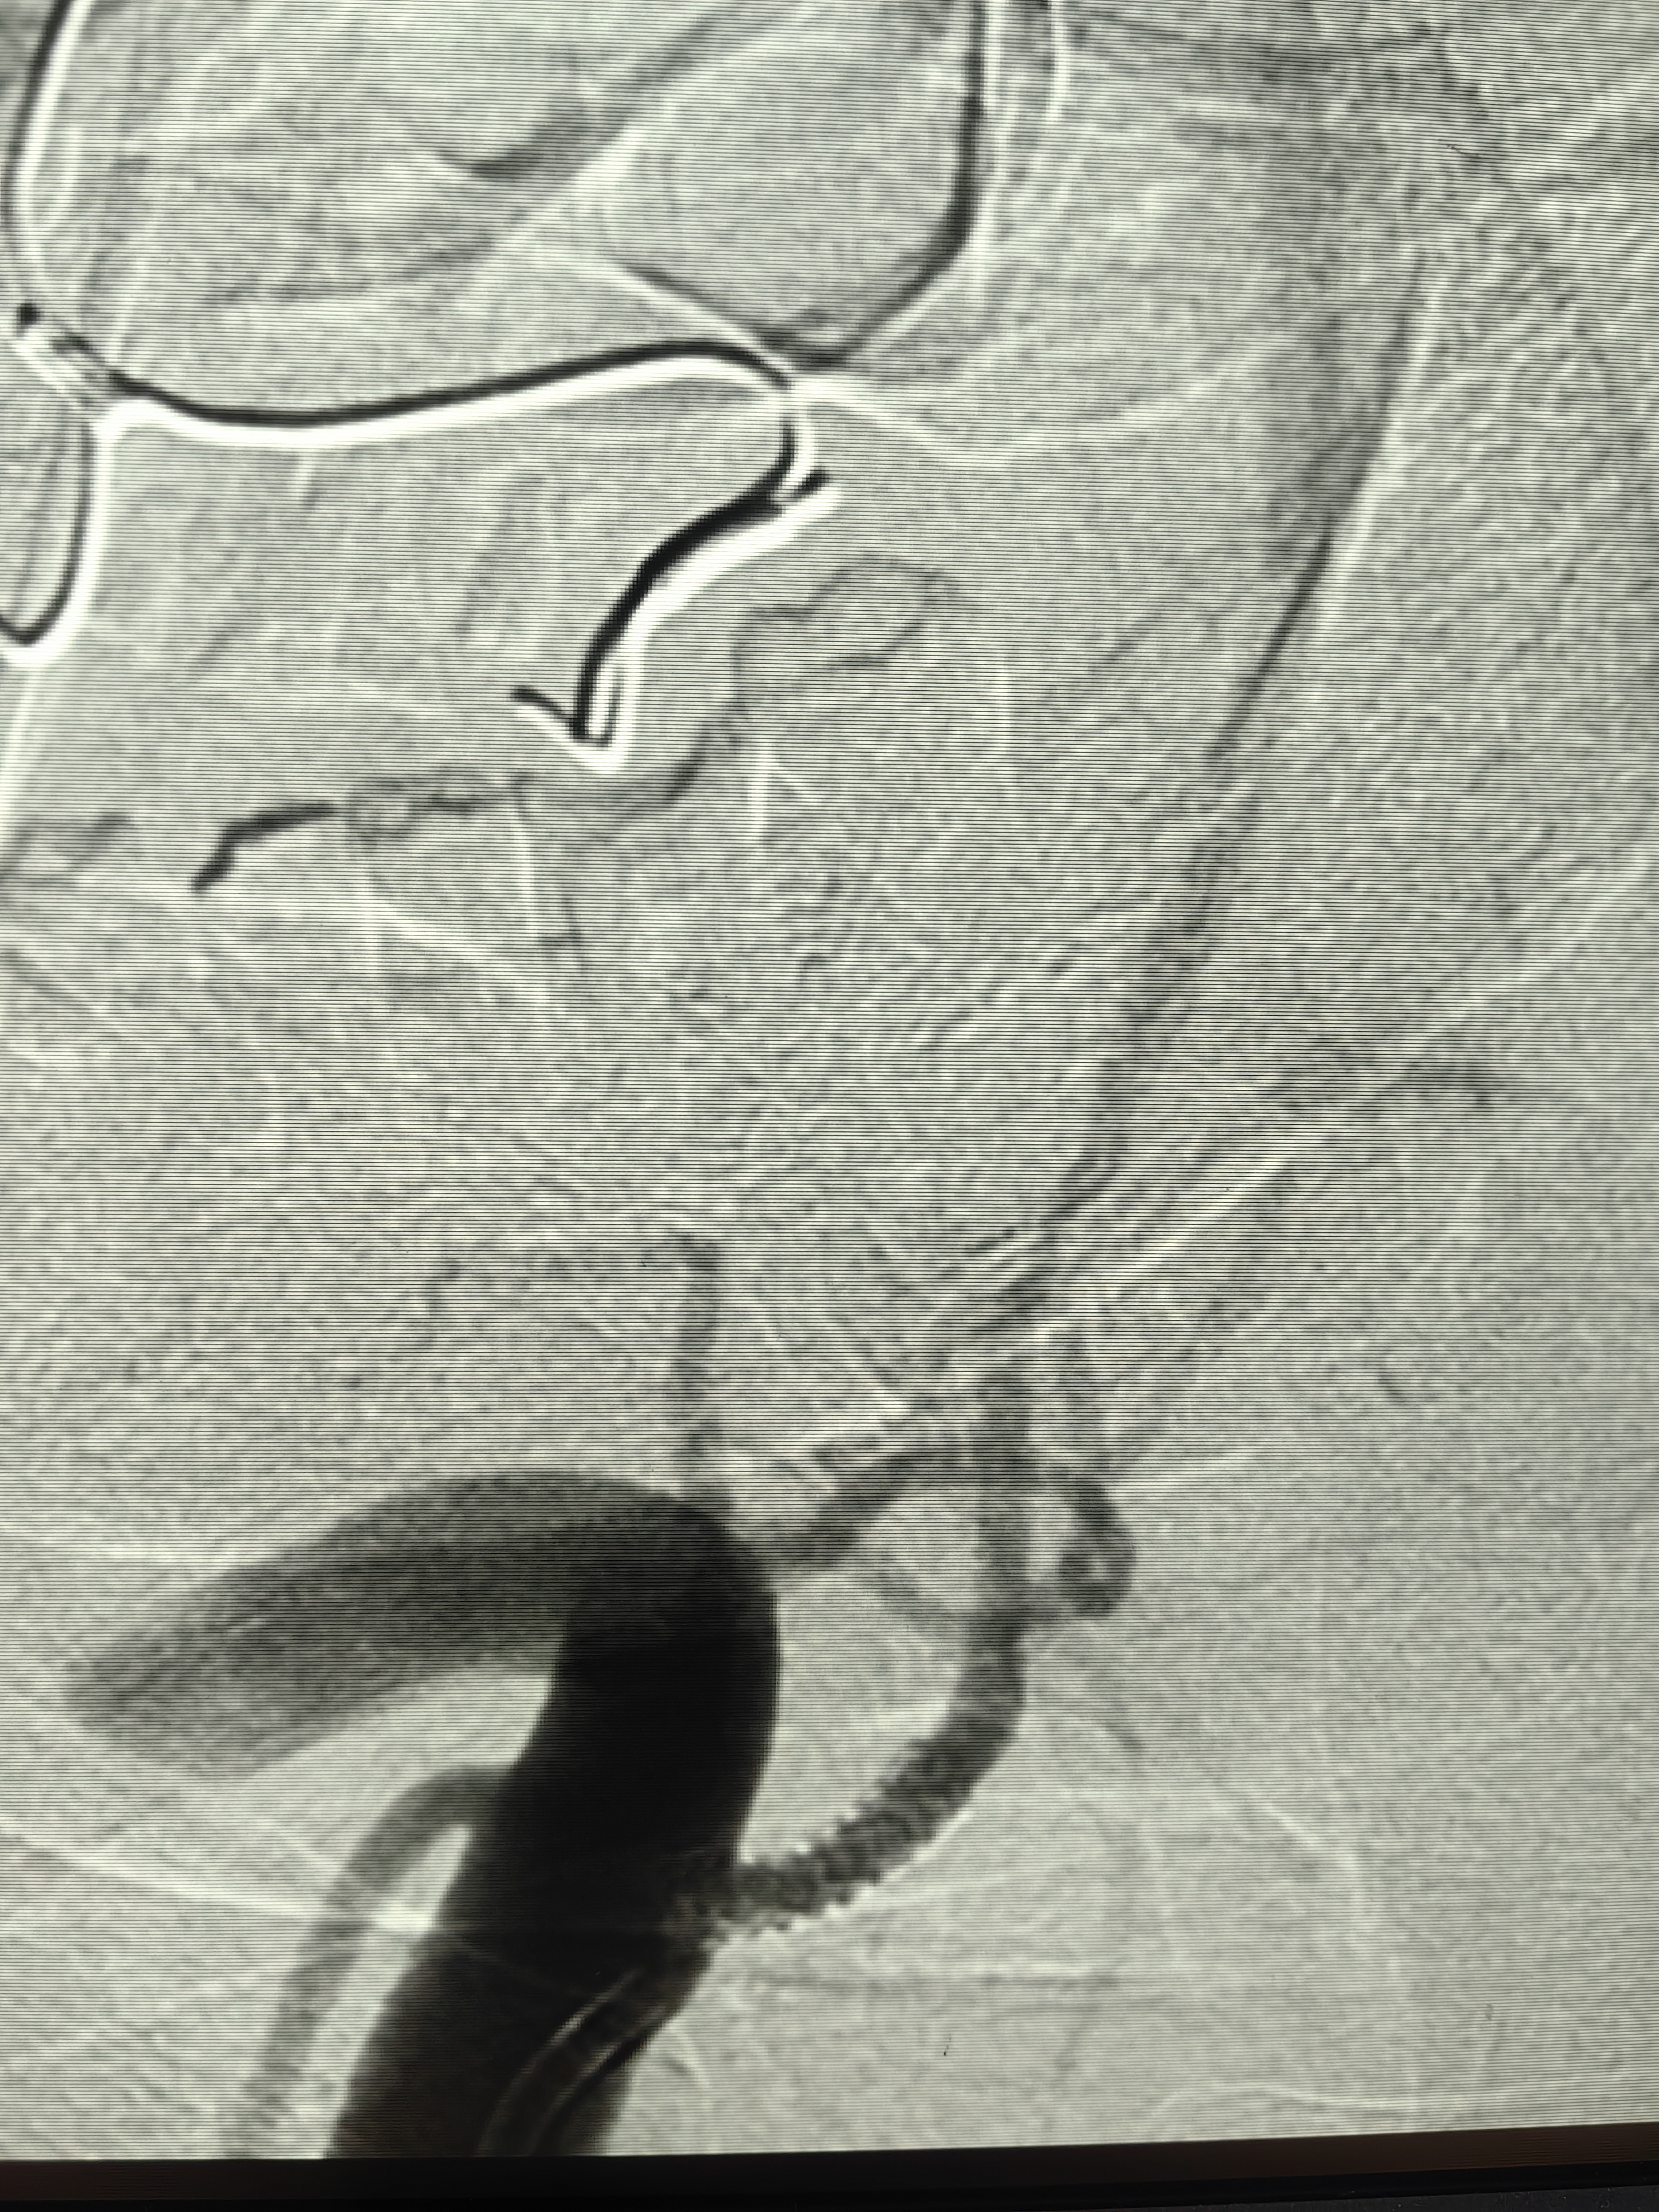

通过的一瞬间,甚至都是有多巴胺分泌的了,可以想象过程有多坎坷😂

我以为微导管通过会稍困难,结果还算顺

接下来的简单了,微导管造影,3m导丝交换,小球囊预扩,支架到位,定位,释放,造影: